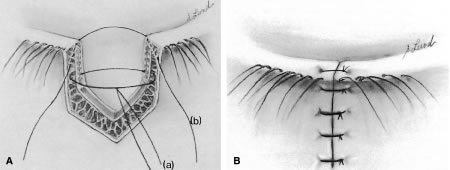

The posterior lamella consists of the eyelid retractor, the tarsus, and the conjunctiva. Hawes and Dortzbach2 reviewed and highlighted lower eyelid anatomy, specifically the lower eyelid retractor (Fig. 1). The lower eyelid is analogous to the upper eyelid; the main variation is the eyelid retractor system. The upper eyelid has a distinct eyelid retractor, the levator muscle, to enhance upper eyelid mobility. The lower eyelid does not have a specialized eyelid retractor. The lower eyelid retractor system originates as a fascial extension of the inferior rectus muscle (capsulopalpebral head). This fascial system splits to encapsulate the inferior oblique muscle and then reunites to form a dense fibrous sheet (capsulopalpebral fascia) to insert onto the inferior tarsal border. The inferior tarsal muscle is a smooth muscle analogous to the superior tarsal muscle (Müller's muscle) of the upper eyelid. This muscle originates in the inferior fornical area and extends toward the inferior tarsal border but does not insert on the tarsal border as its counterpart in the upper eyelid does. The inferior tarsal muscle receives sympathetic innervation, and interruption of its innervation will result in a slightly elevated position of the lower eyelid margin as observed in Horner's syndrome. Otherwise, the inferior tarsal muscle has little pathologic significance.

The tarsus provides the primary support or foundation for the eyelids. Although degeneration of the tarsus may promote eyelid laxity,3 the principle focus of weakness of the eyelids is at the lateral and medial canthal tendons.4 Jones and Wobig5 described the medial canthal tendon with a prominent anterior component firmly connecting the medial canthal angle to the maxillary process of the frontal bone. The posterior limb of the medial canthal tendon provides deep support to the posterior lacrimal crest. Anderson6 also emphasized the role of a superior branch of the medial canthal tendon to support the canthal angle. Gioia and coworkers7 have provided a clear description of lateral canthal anatomy. The lateral canthal tendon has contributions from the lateral aspects of the tarsus and the preseptal and pretarsal orbicularis muscle; these insert on the inner aspect of the lateral orbital rim at Whitnall's (lateral orbital) tubercle. The posterior deep insertion of the lateral canthal tendon allows the lateral aspect of the eyelids to approximate the globe.

Involutional entropion is more complex because of the multitude of factors producing this abnormality. The tarsal instability of entropic lids is due to horizontal eyelid laxity and loss of support of the lower eyelid retractors.10 The orbicularis muscle dynamics also assume a prominent pathophysiologic role in the production of entropion. In entropic eyelids, the preseptal orbicularis muscle overrides the pretarsal orbicularis muscle, which rolls the superior border of the tarsus internally. This is differentiated from spastic entropion, which is theoretically due to a spasm of Riolan's muscle. However, the primary differentiating feature of spastic entropion is a specific precipitating etiologic factor, such as recent eye surgery, eyelid edema, or ocular inflammation with secondary eyelid edema. An appreciation of the multiple etiologic causes of entropion has resulted in the evolution of combined approaches to correcting the various anatomic abnormalities and stabilizing the tarsus and orbicularis muscle.11–14